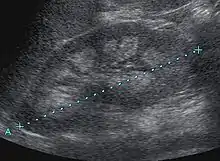

| Bilateral nephrocalcinosis seen on an abdominal x-ray | |

Nephrocalcinosis is diagnosed for the most part by imaging techniques. The imagings used are ultrasound (US), abdominal plain film and CT imaging.[10] Of the 3 techniques CT and US are the preferred modalities.